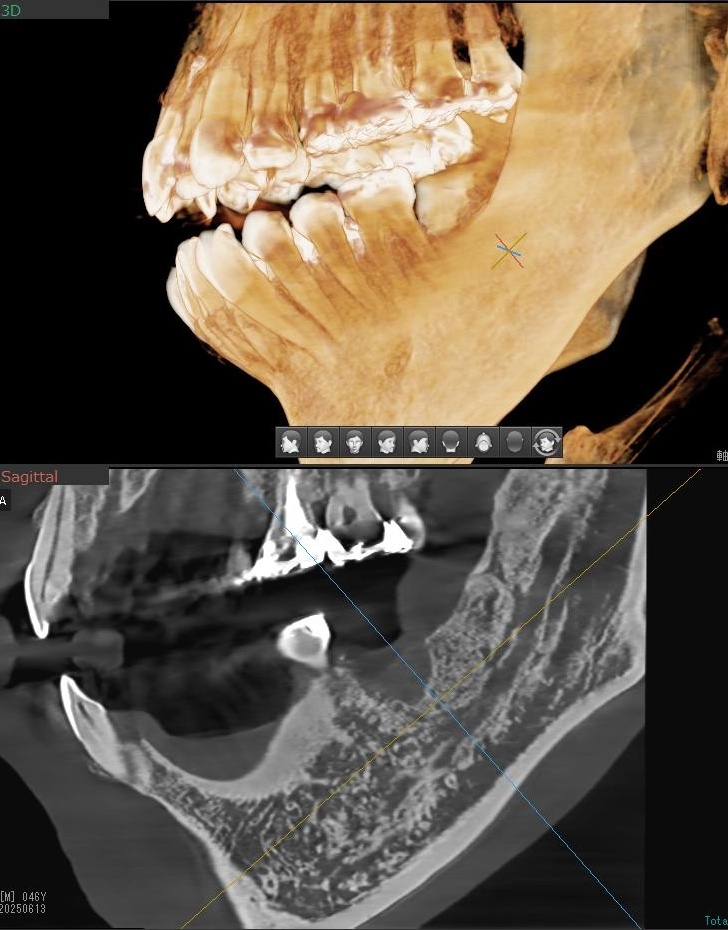

今回の患者様はインプラント植立を希望され、左下7番目、1本の植立が決まりました。

しっかりとインプラント埋め込まれた後は、動揺がないか、噛んだ時に当たらないかなどを確認して、最後にパノラマ写真を撮影して今回のオペは終了となりました。